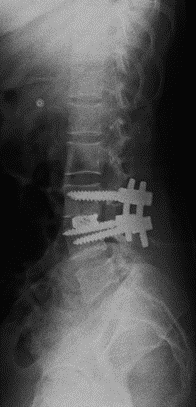

At presentation she had severe paraspinal spasm with movement restriction and no neurological deficits. Radiographs revealed a minimal reduction in L4/5 disc space . Hematological evaluation elevated showed TLC, ESR, CRP. MRI showed evidence of discitis at L4/5 with adjacent vertebral reactive changes( FIG 1,2). With a working diagnosis of post partum spondylodisctis she underwent a septic screening ( sputum, urine, blood cultures) and a CT guided biopsy which turned out to be negative. Considering her significant back pain  with limitations in suggesting antibiotics  she was suggested surgical debridement and fusion at L4/5. She underwent PLIF L4/5 under GA and had a drastic early pain relief . She was mobilized on post operative day – 1 with lumbo sacral brace. Her pain reduced significantly ( VAS 2/10) which needed minimal analgesics ( once a day paracetamol 1 gm intravenous infusion )for 5 days . She was able to turn in bed and sit to nurse the child. Her intraoperative tissues sent for culture grew pseudomonas which was sensitive to cefaperazone + sulbactum. She was initiated on intravenous antibiotics for 2 weeks duration and was followed up with further 4 weeks of oral antibiotics . Radiographs revealed fusion at L4/5 at 3 months( FIG 3,4) of follow up with serological markers normalizing by 6 weeks.

Fig 3: L4/5 PLIF- AP view

Fig 4: L4/5 PLIF- Lateral view